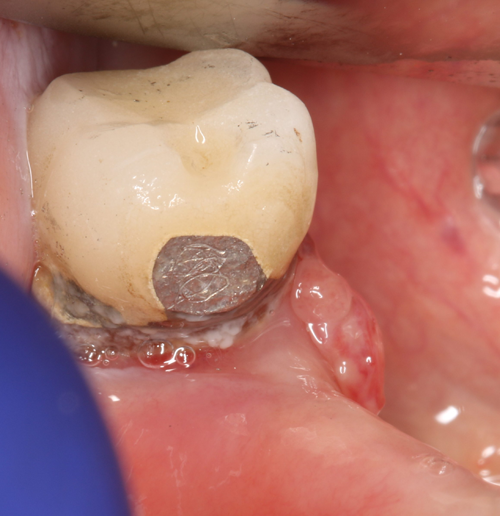

Figure 1 shows an example of a deep subgingival margin with the ensuing bleeding. If we are planning on packing a cord, we need to pack multiple cords soaked in hemostatic agent and wait for the soft tissue to move away from the tooth margin and achieve hemostasis. We have all experienced the moment of truth when the cord is removed, which oftentimes reinitiates the bleeding and the soft tissue again flops over the tooth margin, making it almost impossible to get an adequate impression the first time. This results in the loss of time, incurred cost of another tray full of material and the patient needing to undergo a mouthful of gagging material.

Compare this to use of the Gemini laser. We can set the power setting of the laser using the preset power settings for “Troughing” (Fig. 2) at 1.1 watts. The pre-initiated tip (pigment on the laser fiber converts some of the laser energy to photothermal energy) is placed into the sulcus to ablate the soft tissue, which creates a clear separation of the soft tissue from the tooth margin and achieves instant hemostasis (Fig. 3). We then have no need to wait and can immediately take the impression (Fig. 4). I consider this alone as priceless in my day-to-day practice.